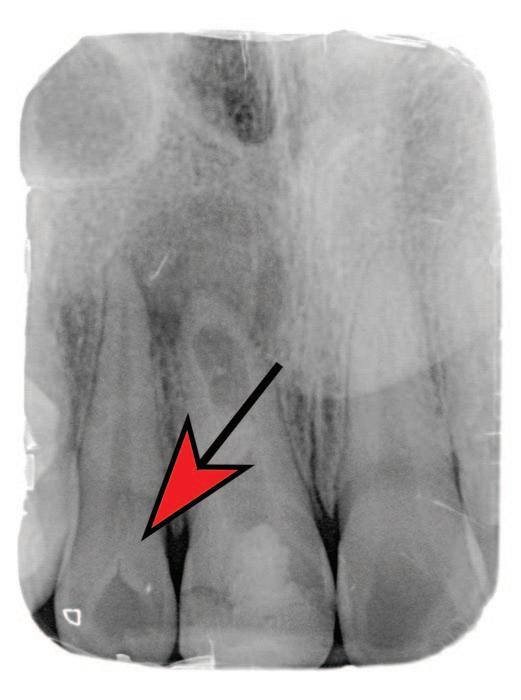

Table 1: Merged-ICDAS visual coronal caries stages.4

Merged-ICDAS score Code Description

Sound (ICDAS 0) 0

Initial caries lesions (ICDAS 1-2) A

No evidence of change in enamel translucency due to caries after plaque removal and air drying

Changes in enamel seen as a caries opacity or visible discolouration (white/brown spot) not consistent with clinical appearance of sound enamel, with no evidence of surface breakdown, no underlying dentine shadowing and no cavitation

Moderate caries lesions (ICDAS 3-4) B3

White/brown spot lesion with localised microcavity/discontinuity, without visible dentine exposure. Best seen after air drying B4 Obviously discoloured dentine visible through apparently intact or microcavitated enamel surface, which originated on the surface being evaluated. Often seen easiest with the tooth surface wet

Extensive caries lesions (ICDAS 5-6) C Obvious visible dentine cavity in opaque/discoloured enamel. A WHO/CPI/PSR probe can gently confirm if the cavity extends into dentine

2. Assess the staging of the coronal carious lesion